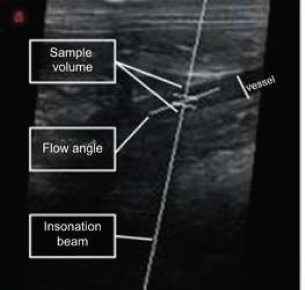

Fig. 6. Image of the abdominal aorta of a cat, showing the sample volume, ultrasound beam, and main flow vector, with the latter overlaid and parallel to the vessel being evaluated with spectral Doppler. Source: Personal archive, 2025.

Pulsed spectral Doppler signals

This technique measures flow velocity using piezoelectric crystals that emit ultrasound sound pulses and analyze the reflected signal. The sample volume (or “gate”) was adjusted in B mode to locate the area of interest (Szatmári, et al., 2001; Carvalho et al., 2008a). The accuracy of the Doppler decreases with angles close to 90°, and the data are processed via Fourier transform to generate graphs with Fd on the vertical axis and time on the horizontal (Carvalho et al., 2008b), as illustrated in Figure 6. The duplex image combines Doppler and B-mode images in real time, facilitating interpretation (Carvalho et al., 2008a).

In the morphological analysis of arterial spectral waves, classification can be based on the velocity profile and the resistance of the flow. In terms of velocity profile, flows can be laminar, where the blood moves in concentric layers, or turbulent. Within laminar flows, there are the following classifications (Jenderka and Delorme, 2015; Kim et al., 2020): Flat flow (Fig. 7): in large arteries (e.g., aorta), where the velocity is uniform, forming a spectrum with a wide spectral window (Chavhan et al., 2008; Miño et al., 2008; Jenderka and Delorme, 2015).

Fig. 7. Spectral Doppler of the aorta, characterized by flattened and high-resistance flow. A thin line is observed in systole surrounding a clear space, known as the spectral window. Source: Personal archive, 2025.